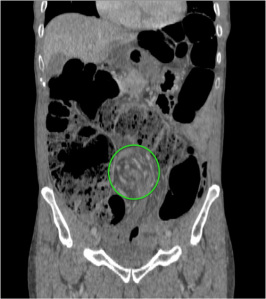

El diagnóstico actual de la se realiza mediante TC abdominal:

- El hallazgo patognomónico es el signo de la escarapela o diana identificable en la TC o ecografía.

- Podemos ver la imagen de “Intestino dentro de intestino” gracias a las reconstrucciones multiplanares.